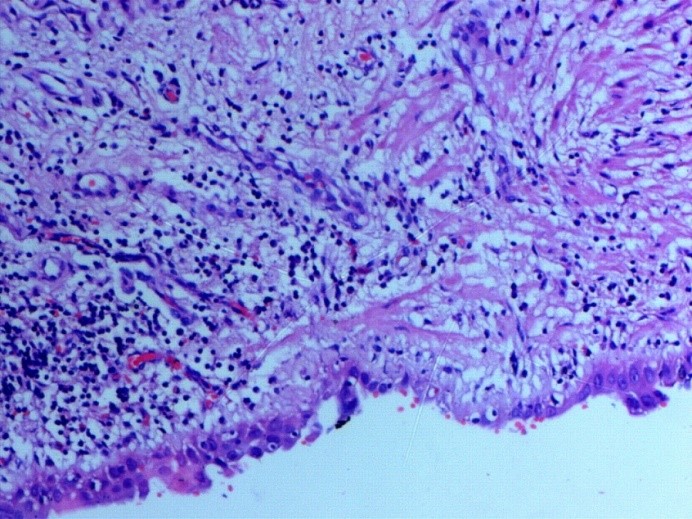

After the operation, the patient was stable. A postoperative chest CT scan showed good expansion of the left lower lobe. Pathological result showed a cystic lesion of the lobe (Figure 3). The patient was discharged five days after surgery.

Bullae are associated with malignancy and can cause a lot of complications, such as pneumothorax and infection (9). In the authors’ study, pathology showed a cystic lesion of the lung. Lobectomy was indicated not only for treatment of the giant bulla, but also for the prevention of complications and malignant transformation.